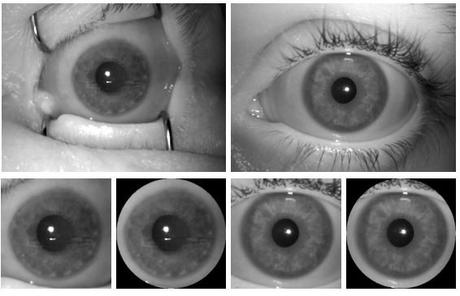

Mateusz Trokielewicz, doctorado en Biometría en la Universidad Tecnológica de Varsovia, se preguntó hace tiempo '¿Qué pasa si me roban un ojo?'. La consecuencia de esta pregunta se cristalizó en miles de horas de laboratorio haciendo fotografías a varios cadáveres a lo largo de 33 días.

La metodología fue sencilla. Tras el fallecimiento se hacía un escáner ocular al iris del cadáver y luego una fotografía cada pocas horas. En total, él y su equipo acabaron reuniendo 574 imágenes del iris de 17 cadáveres. Más 256 imágenes del iris de personas vivas.

Con todos estos datos comprobaron los sistemas de seguridad actual, pero también entrenaron una IA para que adivinase si alguien estaba vivo o muerto en base a la fotografía de su iris. ¿El resultado?

"Ningún iris post mortem se clasifica erróneamente como vivo, con una probabilidad de clasificar erróneamente una muestra viva como una muerta alrededor del 1%". Pero hay un asterisco enorme: durante las primeras 16 horas la IA no es capaz de asegurar si la persona está o no viva.